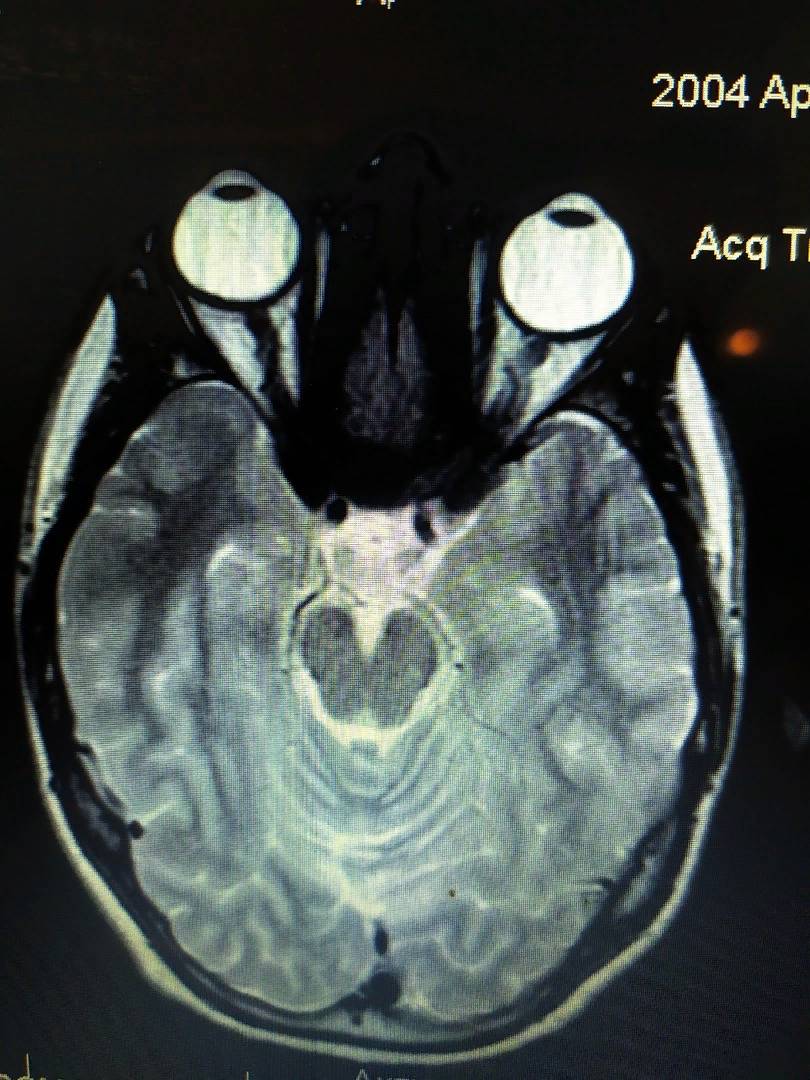

Вот вам ещё один пример томографии.

Рис 4. Авторская иллюстрация (томография могза)

Обратите внимание, глаз справа (на картинке) больше чем левый. На нём -6.25 диоптрий. А на левом -4.5 дптр. Разница всего на 1.75 дптр, но длина глаза уже заметно различима. И заметьте: глаз справа БОЛЬШЕ и в длину и в ширину. Он не сплюснут и вытянут, а он просто вырос, стал больше (в результате процесса адаптации под близь).